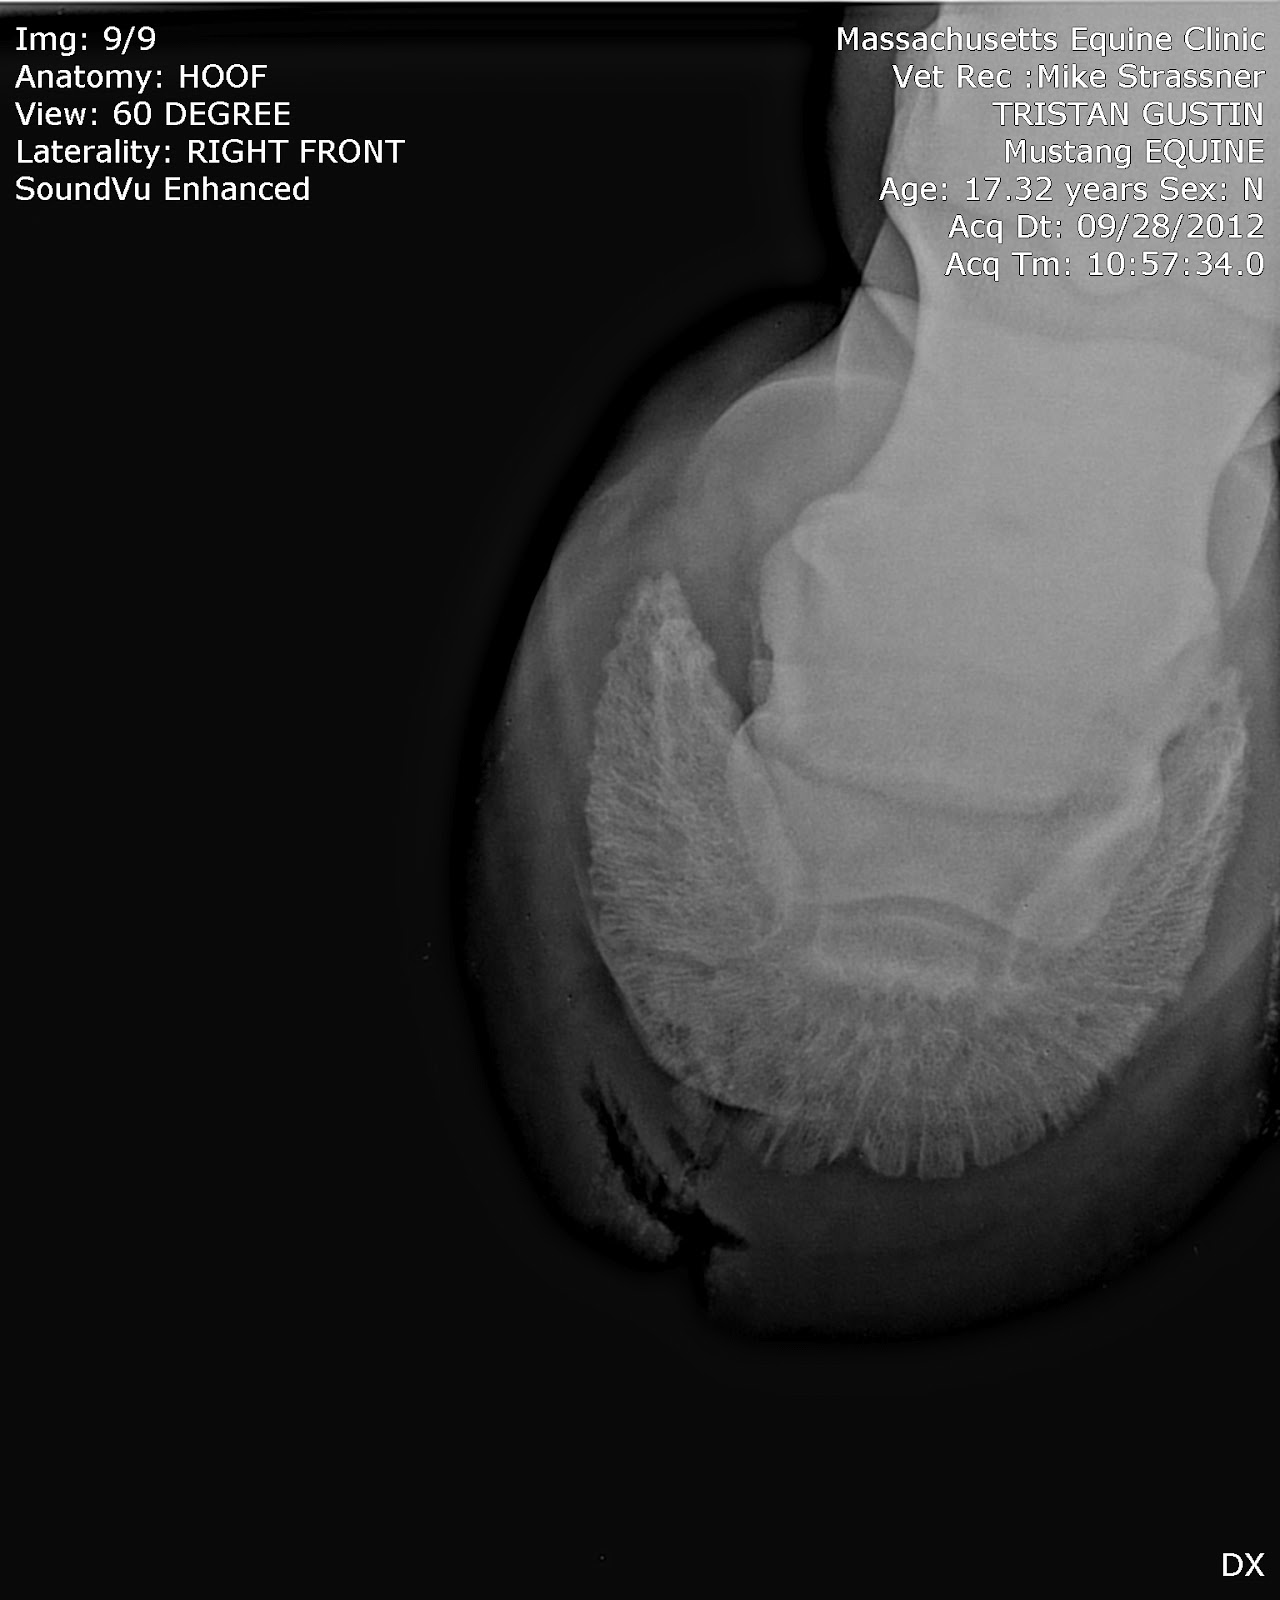

| And the top-down view of the hole, showing its width as well. Eek. |